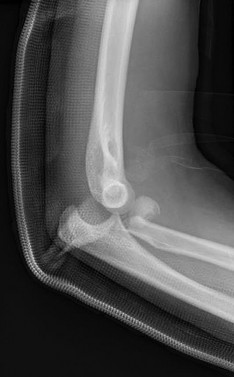

A 45-year-old male sustains the injury pattern depicted in the provided image. During surgical reconstruction of the lateral collateral ligament complex, identifying the correct isometric origin of the lateral ulnar collateral ligament (LUCL) on the distal humerus is critical. Where is this point located?

Correct Answer: At the center of the axis of rotation of the capitellum

Explanation:

The isometric point for the LUCL origin on the humerus is the center of the axis of rotation of the capitellum. Placing a graft or suture anchor at this specific geometric location ensures that the reconstructed ligament maintains relatively constant tension throughout the elbow's entire arc of flexion and extension.